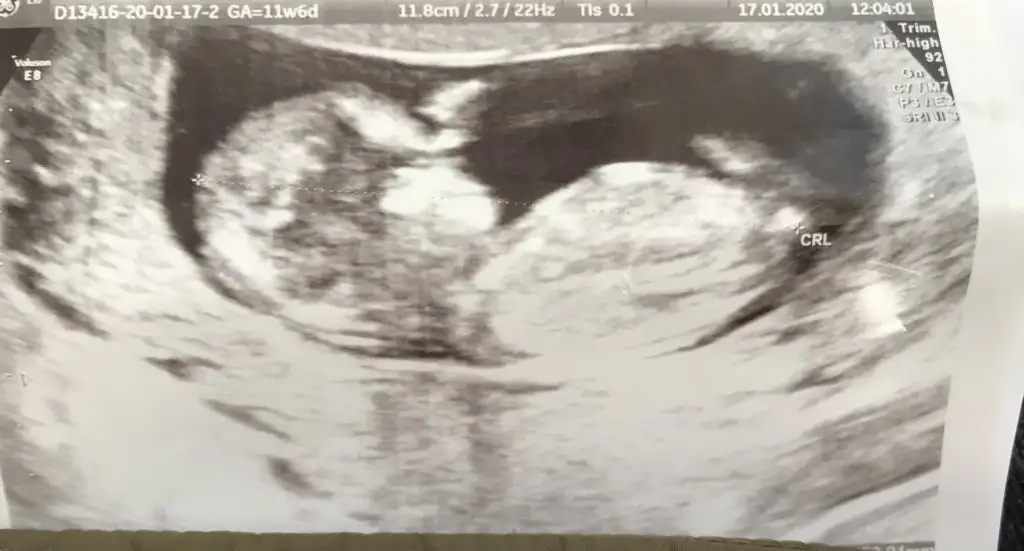

10. Haftadayız. Belki daha erken ama yinede tahmin rica edebilir miyim?😊